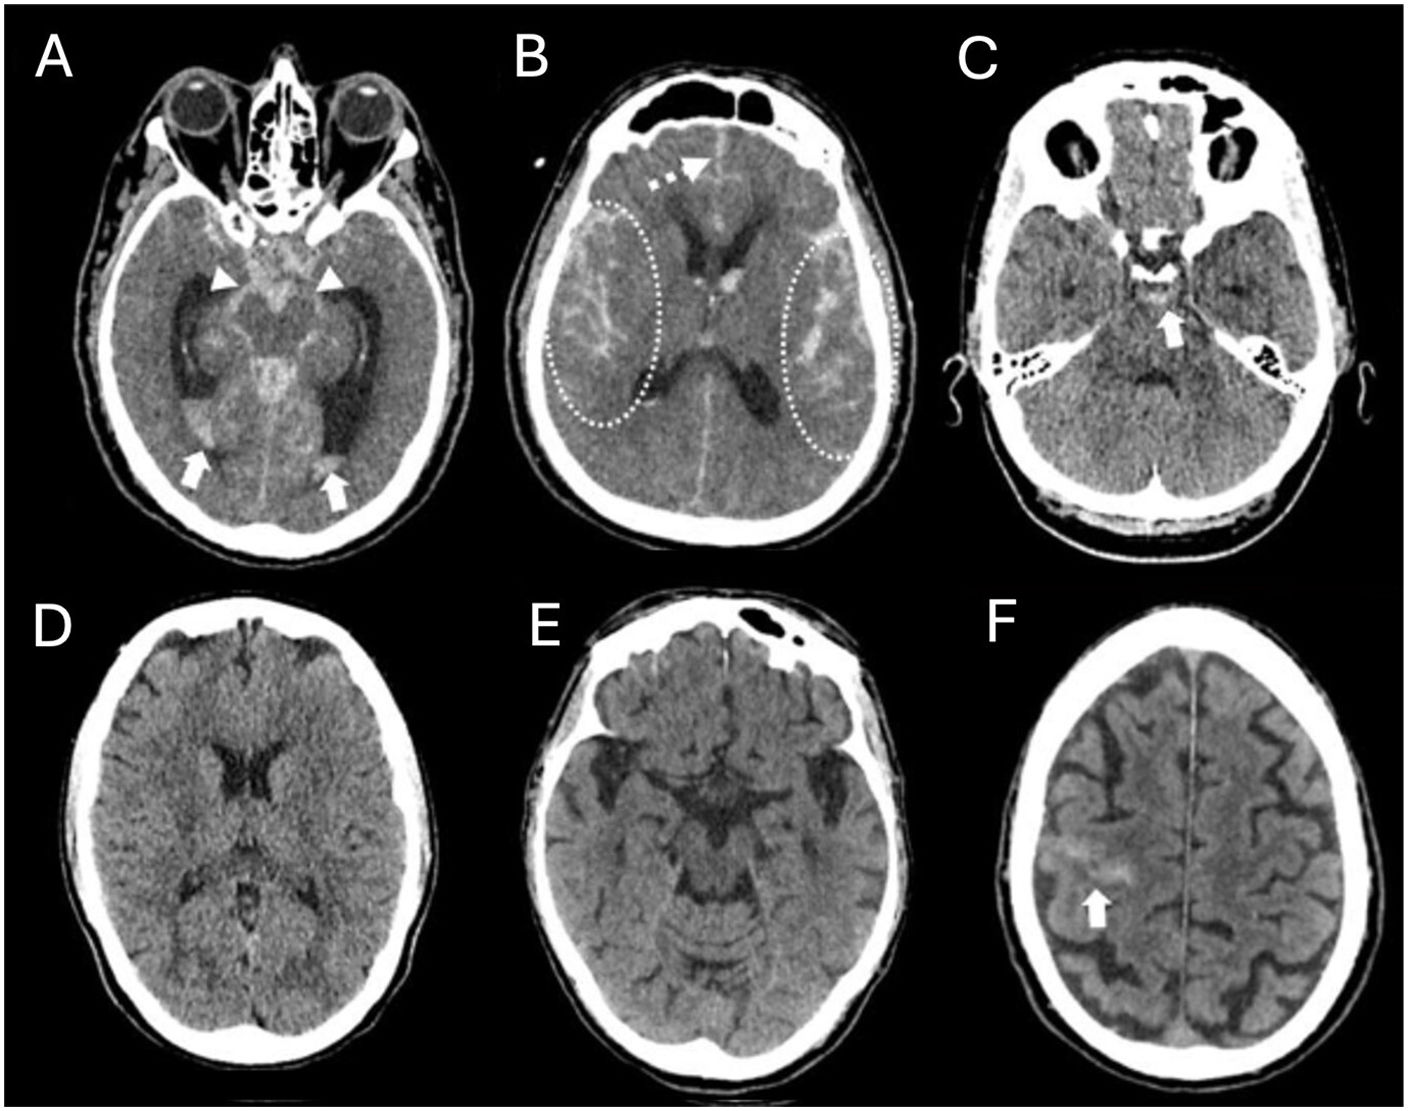

Spontaneous subarachnoid haemorrhage (SAH) is a neurological emergency that predominantly affects young adults, with a high mortality rate and severe neurological sequelae in survivors. Its most characteristic clinical manifestation is a sudden thunderclap headache, often described as the worst headache of one's life, and frequently accompanied by altered levels of consciousness and neck stiffness. Non-contrast cranial computed tomography (NCCT) is the initial diagnostic tool of choice due to its high sensitivity. Recognising the distribution patterns of haemorrhage on NCCT helps guide the aetiological diagnosis and assess the presence of complications such as hydrocephalus, intraventricular haemorrhage or cerebral oedema. This article offers a practical and detailed imaging-based guide for radiologists in the hyperacute phase of spontaneous SAH, distinguishing between aneurysmal, perimesencephalic and cortical patterns, and discusses their clinical, diagnostic and therapeutic implications.